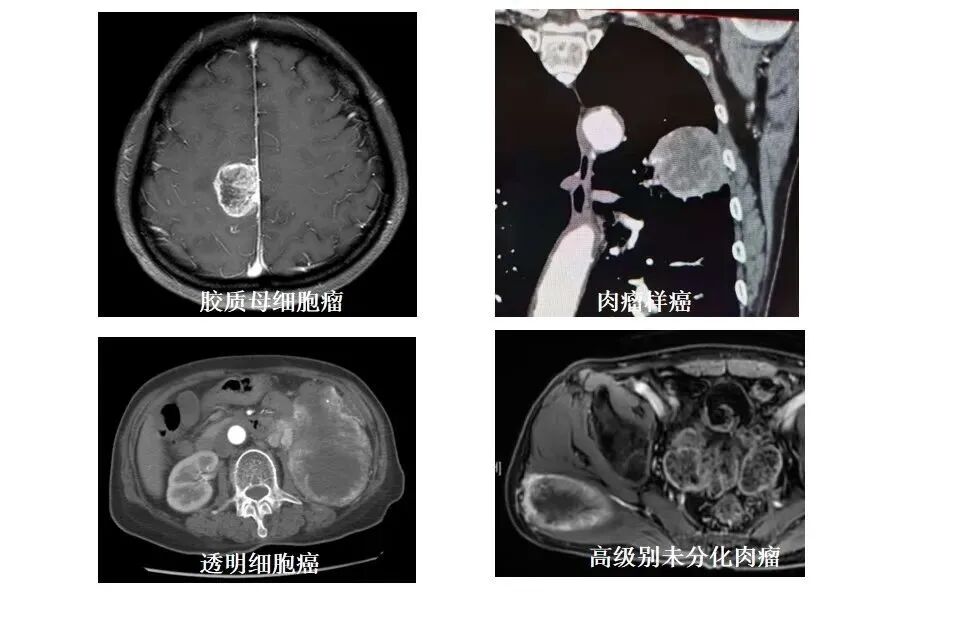

为什么这些恶性肿瘤的坏死边缘这么不规则,不如脓肿和囊变那么清晰规则呢?

怎么买病理图文这些影像征象背后的病理基础,今天才知道!_https://www.jmylbn.com_新闻资讯_第9张

肿瘤的血管是参差不齐的,如同树根一样,攀枝错节,细胞围绕在血管周围获取养分,当一根血管堵塞(内皮损伤、癌栓形成、压迫、侵犯等),所供应的周围细胞就会缺血坏死(凝固性坏死或液化坏死),血管闭塞的越多,坏死越明显,而后互相融合成影像上所见的大坏死了;不规则的血管分布,是坏死不规则的基础。

怎么买病理图文这些影像征象背后的病理基础,今天才知道!_https://www.jmylbn.com_新闻资讯_第10张

经常听到肿瘤长太快,血管跟不上而发生坏死,这个是坏死的重要原因之一,长太快说明肿瘤生长旺盛,核分裂象明显,KI-67高,这个好理解,那么为什么同样高增殖,KI-67甚至可达90%的淋巴瘤,坏死反而少呢?